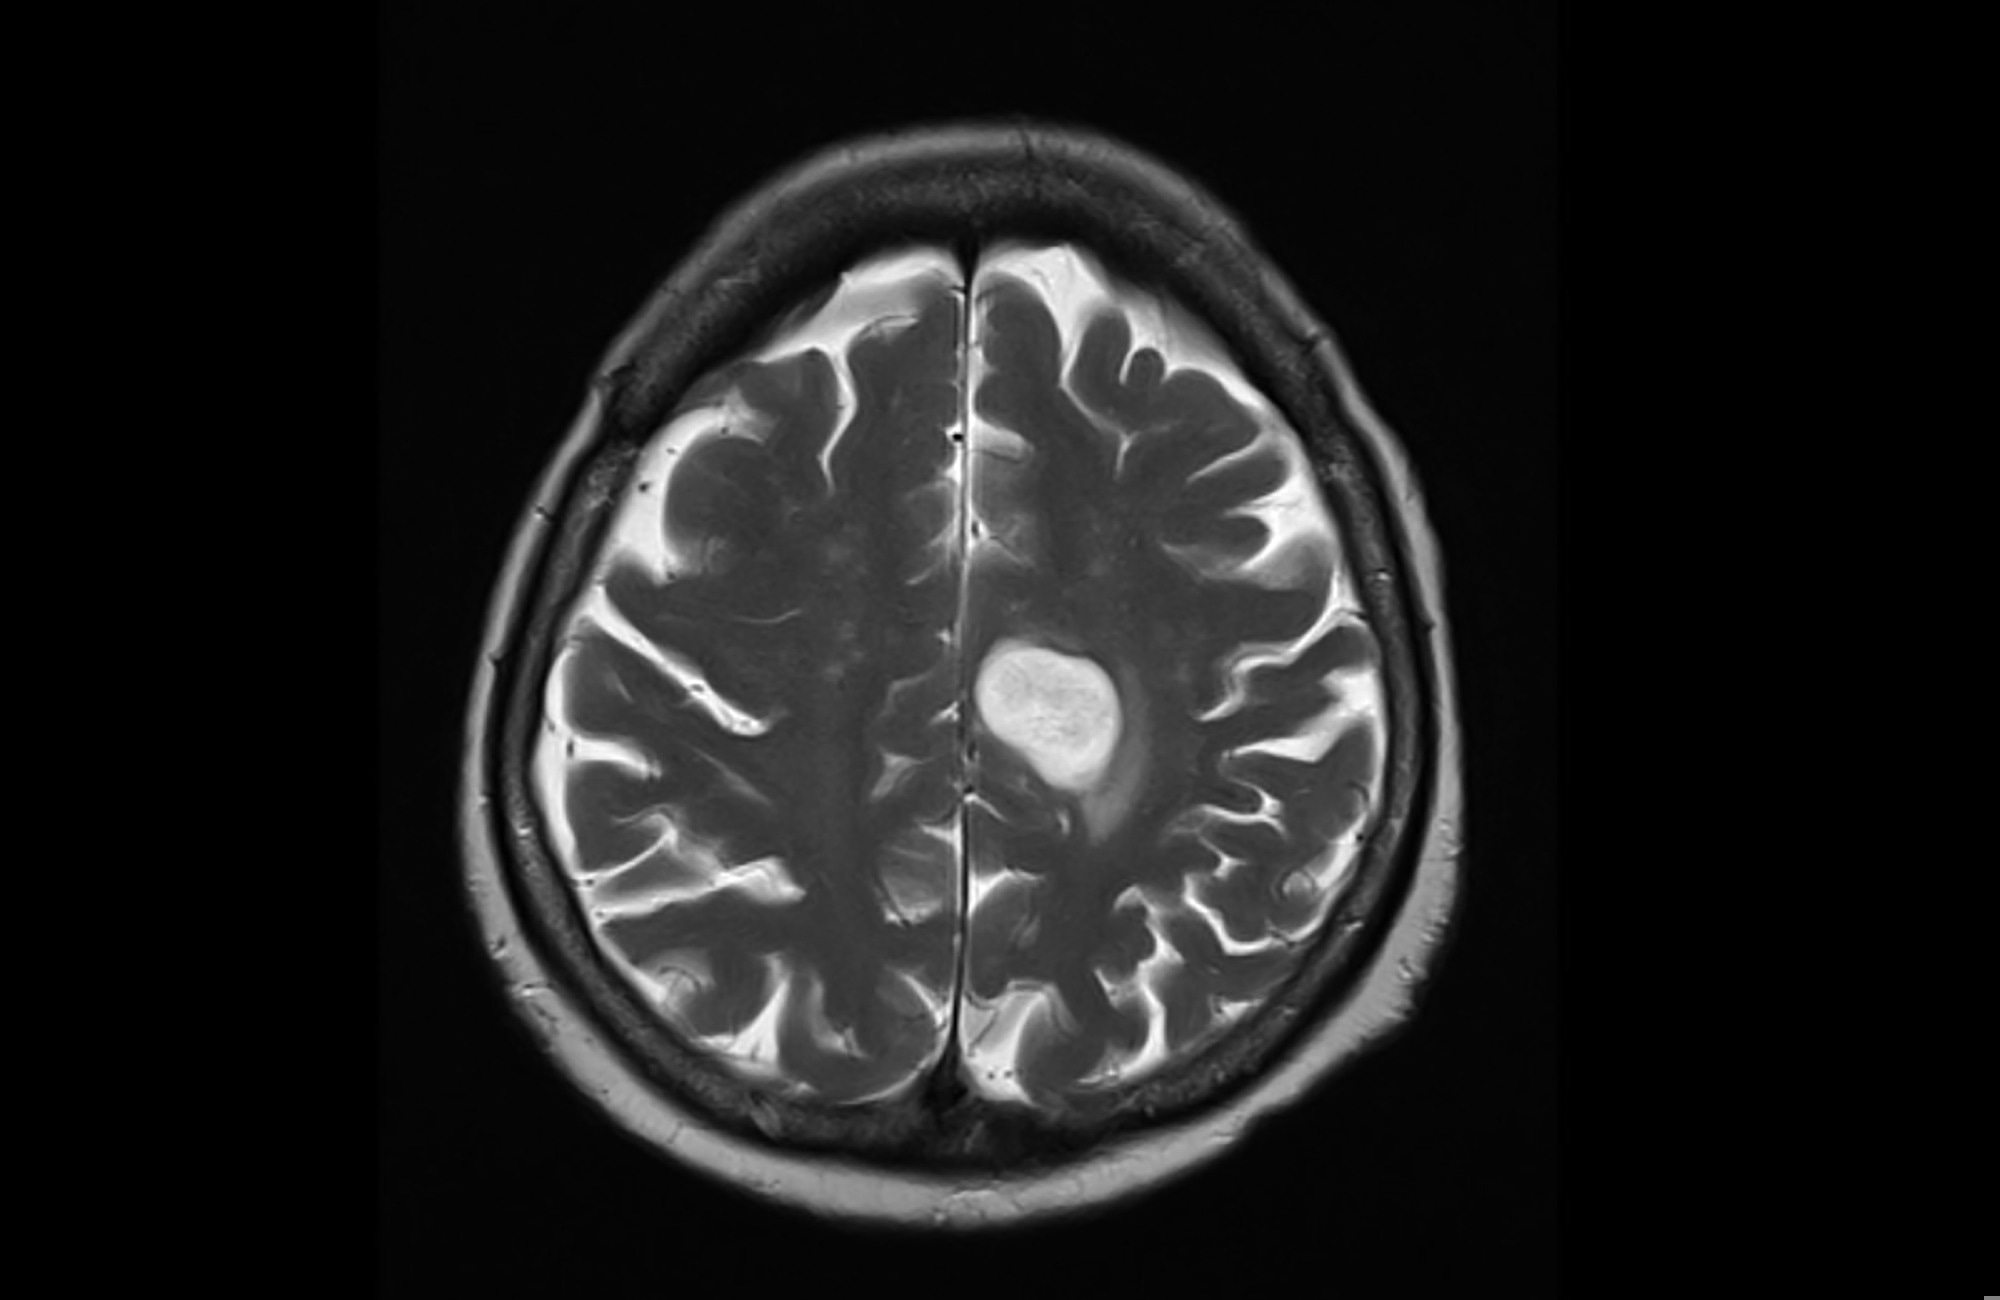

A recent study published in the journal Cancer identifies haloalkane exposure, especially among firefighters, as a risk factor for glioma.

A glioma is a type of brain tumor that arises from glial cells. Based on their aggressiveness, gliomas can be further classified into four grades, with grades I and II considered to be less invasive than grades III and IV.